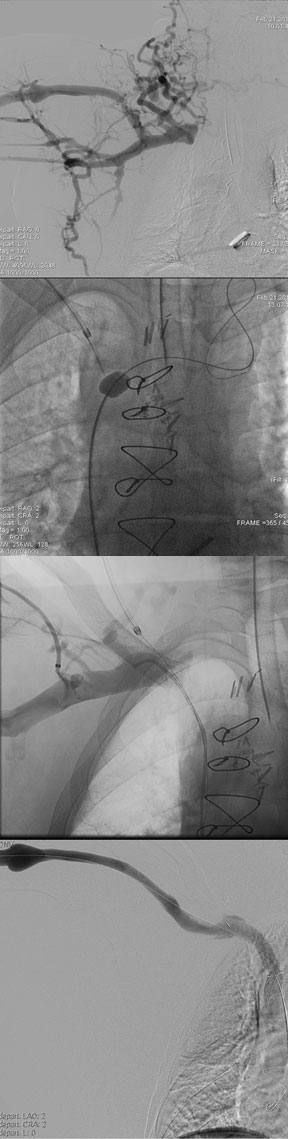

Portal venograms illustrating large gastric varices in a patient with massive upper gastrointestinal bleeding. She underwent transjugular intrahepatic portosystemic shunt (TIPS) placement and balloon-occluded retrograde transvenous obliteration (BRTO) which stopped the hemorrhage.